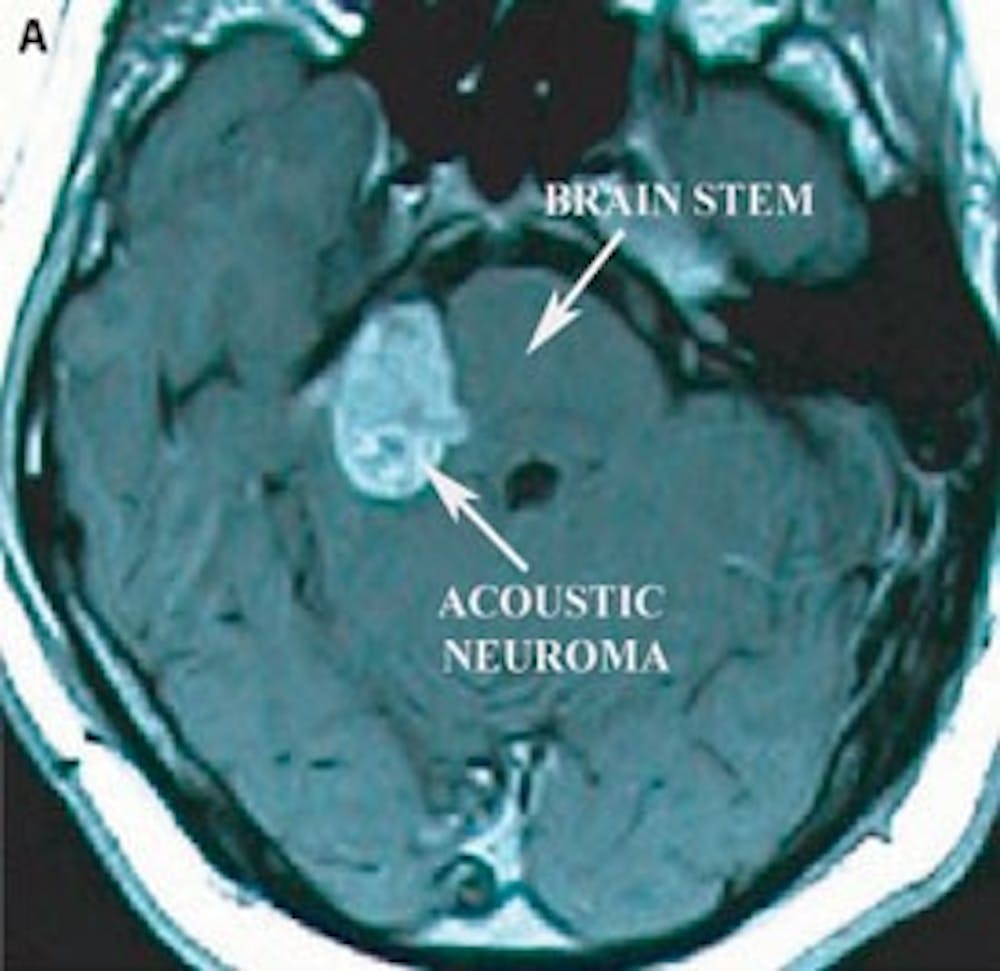

A) 術前軸向 T1 MRI 造影劑顯示大聽神經瘤壓迫腦幹